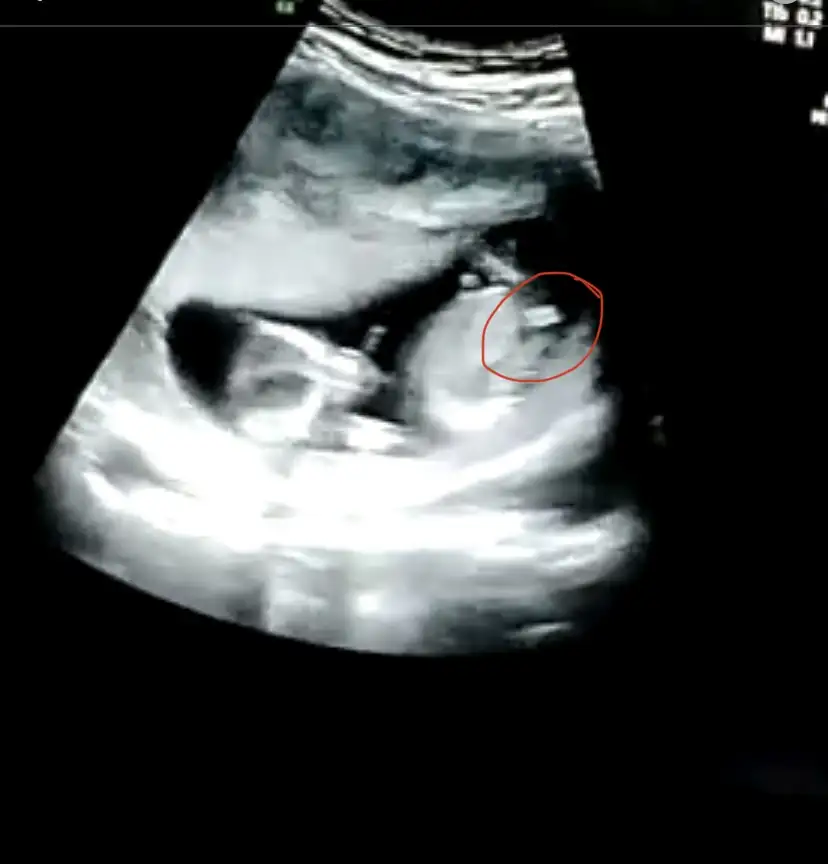

Ikra meyra Ikra meyra mrblar 13 haftalık usg attım kız demiştin canım 14+3 karından bunu da Degerlndirr msn

Ikra meyra Ikra meyra 13 haftalık gebelik canım doktor önce erkek dedi sonra kız da olabilir dedi yorumun var mı